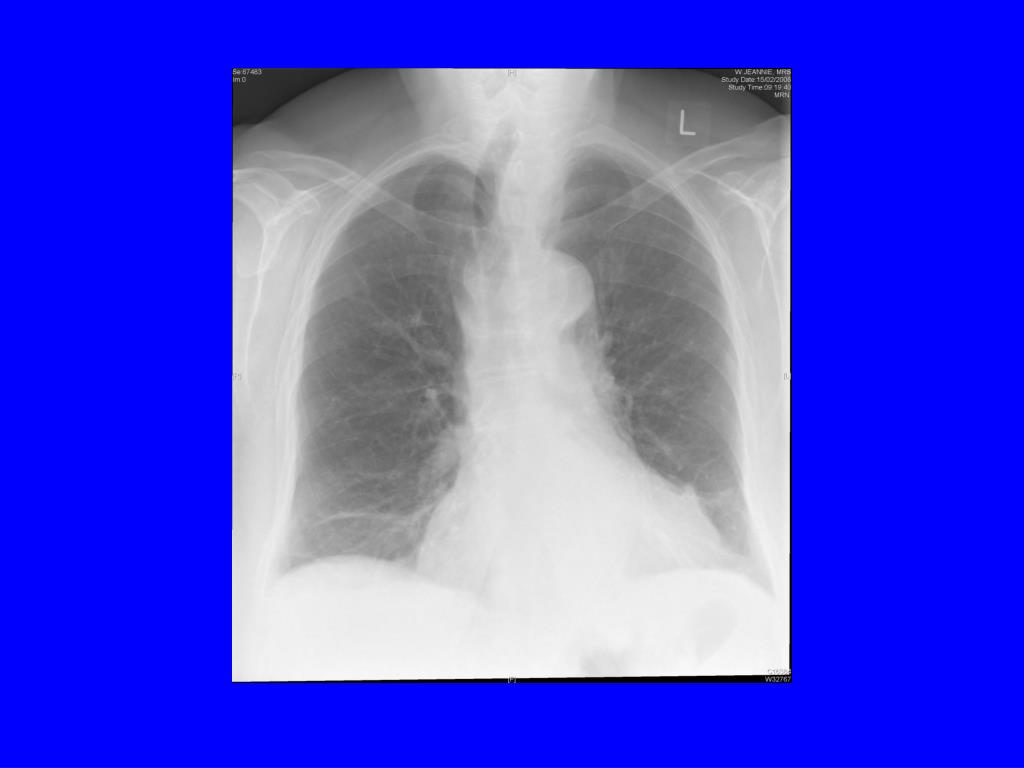

9. Examination • No clubbing or oedema • pulse 72 and regular • heart sounds normal • chest clear • CXR - NAD • FEV1 1.13 53% pred • FVC 1.5l 64% pred, ratio FEV1/FVC 74%

19. Flow volume loops • (a) Normal • (b) - asthma • (c) - emphysema • (d) - restrictive • (e) - upper airway obstruction

27. How can you distinguish cardiac and respiratory causes? • Echo – good biventricular function, LVEF 65%, normal valves, mild TR • ECG – no ischaemic changes • Spirometry – FEV1 1.62 (38% predicted), FVC 3.09, ratio FEV1/FVC 52% • ABG when not acutely SOB – pH 7.426, pO2 6.31, pCO2 7.19 SaO2 82% • CXR